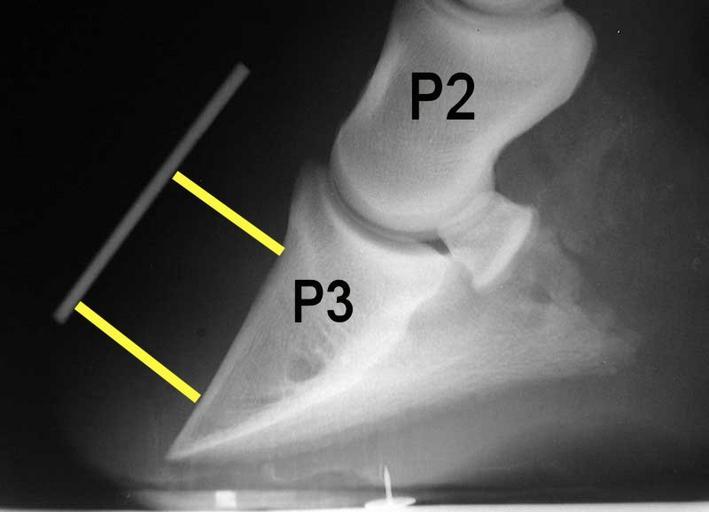

MAKE A MEME View Large Image Laminitis radiograph with annotation.jpg en A typical x-ray or radiograph of a laminitic foot in a horse The annotation P2 stands for the middle phalanx pastern bone and P3 denotes the distal phalanx coffin bone The white line marks the ...

Keywords: Laminitis radiograph with annotation.jpg en A typical x-ray or radiograph of a laminitic foot in a horse The annotation P2 stands for the middle phalanx pastern bone and P3 denotes the distal phalanx coffin bone The white line marks the boundary of the outer hoof wall and the yellow lines show the distance between the top and bottom part of the coffin bone with the outer hoof wall In this example the distal bottom part of the coffin bone is rotated away greater distance from the hoof wall an indication of laminitis Radiograph created by Malcolm Morley annotated by Froggerlaura Malcolm Morley 1999 Laminitis